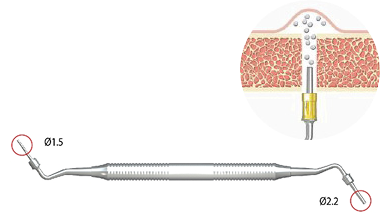

Глубиномер

SADG01